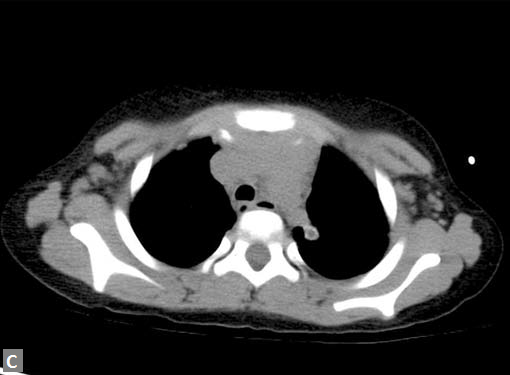

Filling defects (Figs 16A and B) may be seen in main

pulmonary artery (MPA), left pulmonary artery (LPA) and

right pulmonary artery (RPA), interlobar artery, segmental

divisions (Figs 17A and B). On occasions, detection in distal

parts of segmental divisions is difficult. This can be further

confounded by motion artifacts, non- or minimally opacified

accompanying pulmonary veins.

On occasions, thromboembolism can also be seen in right

ventricle and less commonly in pulmonary veins. Systemic

vein thrombus (innominate veins, SVC, IVC) sometimes

accompanies pulmonary thromboembolism (Figs 18A and B).